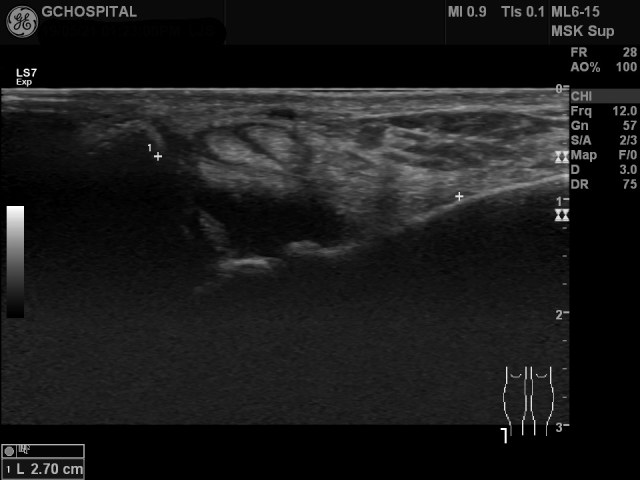

실제로 anterior talofibular ligament가 발목을 어떻게 구부리는가에 따라 길이가 변하는지 초음파영상에서도 확인할 수 있습니다. 인대를 더 길게 늘인 상태에서 관찰해야 인대 자체의 확인도 쉽고, 인대의 손상여부도 민감하게 확인할 수 있습니다.

Anterior talofibular ligament는 위와 같이 platarflexion한 상태에서 훨씬 더 잘 관찰할 수 있는 반면, calcaneofibular ligament는 반대로 dorsiflexion 시 더 길어지고, 잘 보입니다.